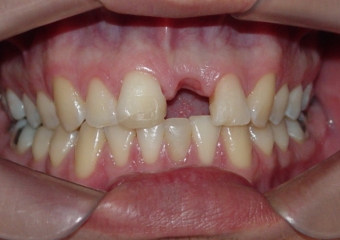

Paciente com ausência do dente 21, por trauma em partida de futebol

Sem a prótese removível